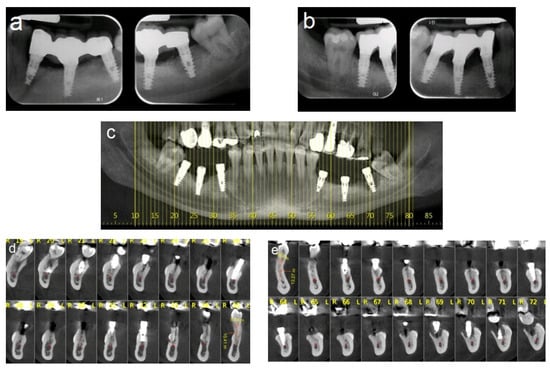

2.5.2. Case 2 (Patient No. 12)

A 47-year-old healthy female patient was referred to our clinic for bilateral augmentation of the posterior mandible and dental implant placement. She was treated using the honeycomb technique and underwent bilateral augmentation of the posterior mandibular ridges. Figure 7 presents the CBCT scans before and after the augmentation procedure (Figure 7a–f), as well as the stable outcomes observed after 13 years of follow-up (Figure 7g,h).

Figure 7.

(a–c) CBCT scan images reveal severe horizontal atrophy in the molar regions bilaterally. (d–f) CBCT scan images taken after honeycomb bone grafting demonstrate significant bone gain. (g); Implants, (h,i) images taken 13-year follow-up after implant loading.